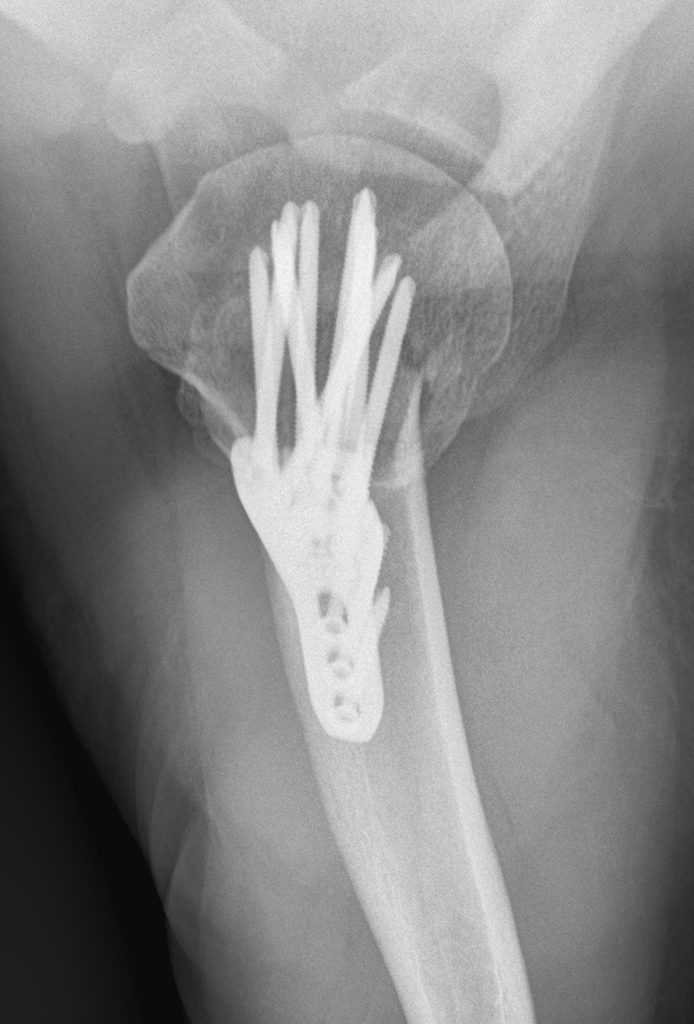

Hallo zusammen Ich hatte im Juli letzten Jahres nach einem Sturz eine humeruskopffraktu + schulterluxation Der arm wurde operiert mit Nägeln und Platten (weiß nicht genau) Ich habe seit dem ersten Tag nach der Op Physio und das 2-3 mal die Woche

Minimalinvasive von schulternahen Oberarmbrüchen Das Medizinprodukt. Wenn ihr zur Klinik vertrauen habt und es sich um eine chrigie handelt, eventuell auch mit anschluß an dierthopädie, dann sehe ich keine bedenken Wir bevorzugen bei komplizierten Brüchen die Stabilisierung mit einer Platte

Oberarmbruch Lumedis Ihre Knochenbruchspezialisten. Nun habe ich bei zwei Ärzten nachgefragt wegen der Entfernung der Platte Diese Osteosynthese ist eine Alternative zum Gipsverband.